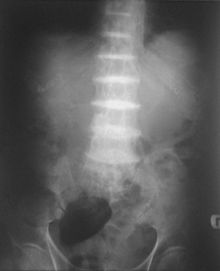

After the age of 30, people begin to develop pain in the weight-bearing joints of the spine, hips, and knees. The pain can be severe to the point that interferes with activities of daily living and may affect ability to work. Joint-replacement surgery (hip and shoulder) is often necessary at a relatively young age.[1] In the longer term, the involvement of the spinal joints leads to reduced movement of the rib cage and can affect breathing.[1] Bone mineral density may be affected, increasing the risk of bone fractures, and rupture of tendons and muscles may occur.[1]

- List of radiographic findings associated with cutaneous conditions